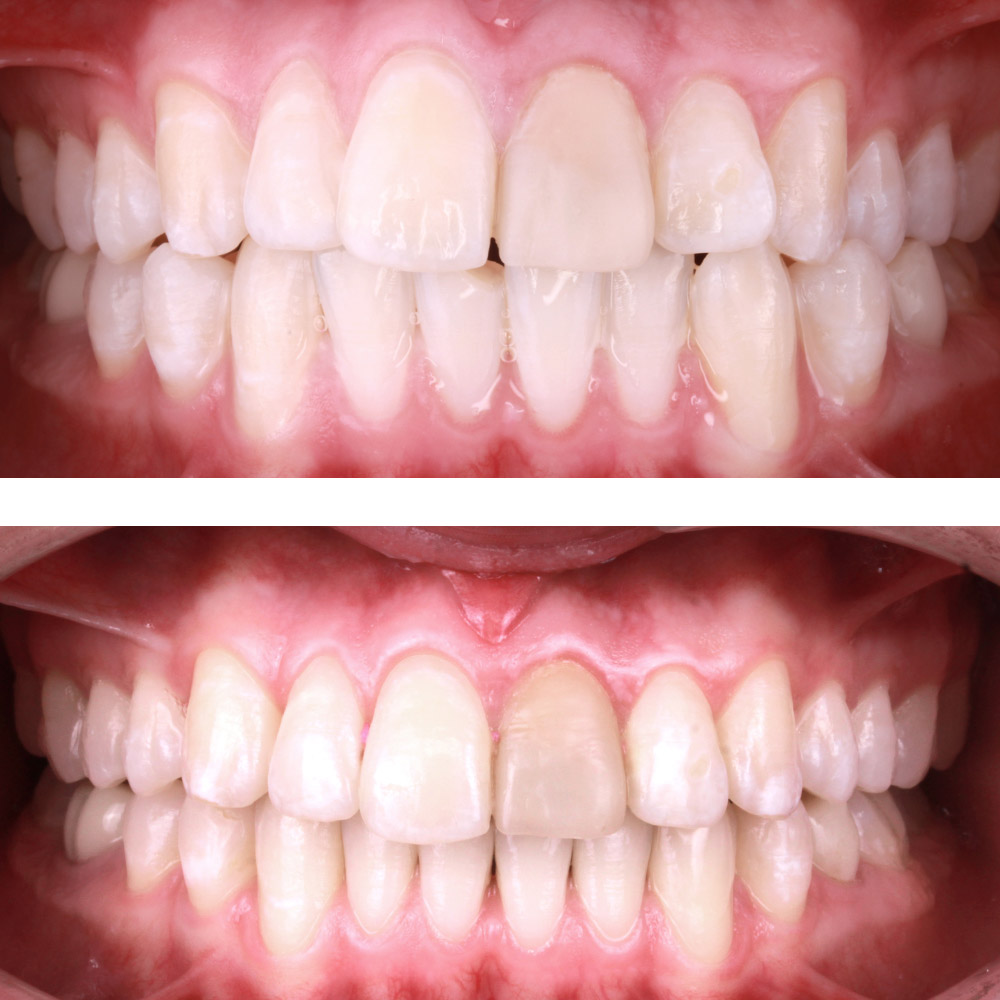

Кейс 9

Бирковская Екатерина Александровна

Количество кап ВЧ 23

Количество кап НЧ 23

ДО

ПОСЛЕ